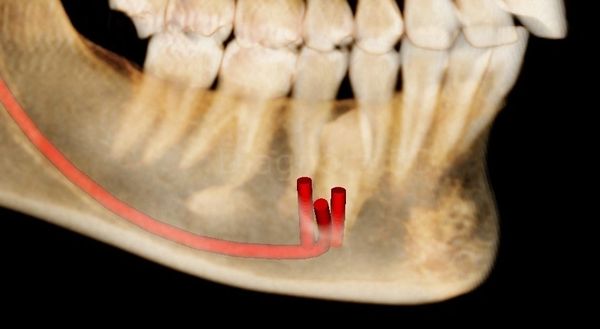

Multiple Mental Foramina - important for surgeries planned in the region, either for dental implants, impacted teeth or periodontal issues